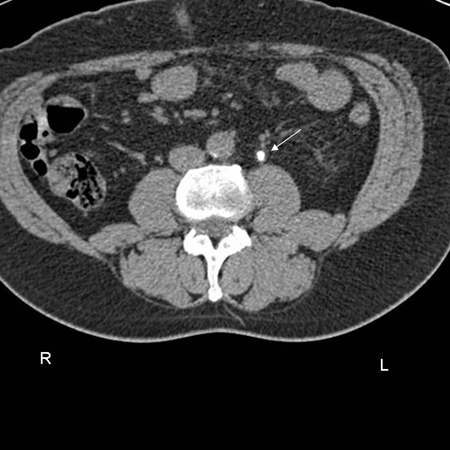

CT scan showing left ureteric calculi

From the personal collection of Dr Kasra Saeb-Parsy